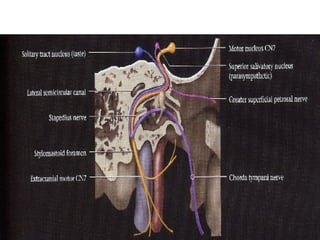

Nervos Cranianos Nervo facial - VII Par 􀂄  Motor 􀂄  Eferente visceral especial 􀂄  M. mímica 􀂄  M. estilo-hióideo 􀂄  M. digástrico-ventre posterior 2° arco branquial 􀂄  Eferente visceral geral 􀂄  Glândulas submandibular sublingual lacrimal 􀂄  Parassimpático

Nervos Cranianos Nervo Facial-Intermédio - VII Par 􀂄  Sensitivo 􀂄  Aferente visceral especial 􀂄  Gustação 2/3 anterior da língua 􀂄  N. lingual 􀂄  N. corda do tímpano 􀂄  G. geniculado 􀂄  Aferente visceral geral 􀂄  Aferente somático geral

Nervos Cranianos Nervofacial - VII Par 􀂄 Motor 􀂄 Eferente visceral especial 􀂄 M. mímica 􀂄 M. estilo-hióideo 􀂄 M. digástrico-ventre posterior 2° arco branquial 􀂄 Eferente visceral geral 􀂄 Glândulas submandibular sublingual lacrimal 􀂄 Parassimpático

Nervos Cranianos NervoFacial-Intermédio - VII Par 􀂄 Sensitivo 􀂄 Aferente visceral especial 􀂄 Gustação 2/3 anterior da língua 􀂄 N. lingual 􀂄 N. corda do tímpano 􀂄 G. geniculado 􀂄 Aferente visceral geral 􀂄 Aferente somático geral